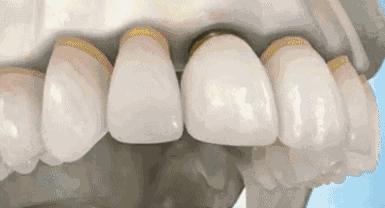

6、死髓牙齿修复治疗

坏死牙髓的牙齿宛如一颗坏死的大树,虽然外面看着依旧挺立,但是内部已经没有了供养。没有爱的供养的树会变得脆弱,没有供养的牙齿也会变得脆弱

这个时候就要及时的给牙齿由内而外的保护起来,内部桩核修复,让牙齿内部坚固。外部冠修复,让牙齿受力均匀,减少碎裂风险。